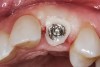

Fig 7. Blanching of the soft tissue.

Figure 7

The provisional is then trimmed of flash and polished, placed into the mouth, and hand tightened. Blanching of the soft tissue is seen as the result of the tissue slumping without the support of the tooth (Figure 7). The provisional is evaluated for proper free gingival margin positioning. The interdental papilla are assessed for volume and height, and the occlusion is checked. If there are any shortcomings, the provisional contours are adjusted. If the gingival margins are more apical than ideal, the cervical area of the provisional is relieved. If the free gingival margin is more coronal than the ideal position, the cervical area of the provisional is bulked out to move the soft tissue apically. Interdental papilla are altered by changing the contact point position, volume, and convexity of the proximal surfaces.10,11 Once the esthetic contours have been developed, a cotton pellet is placed over the screw head, the access hole is filled in with the material of choice, and the occlusion is checked. The goal is to achieve minimal centric contact with no contact in lateral excursions.